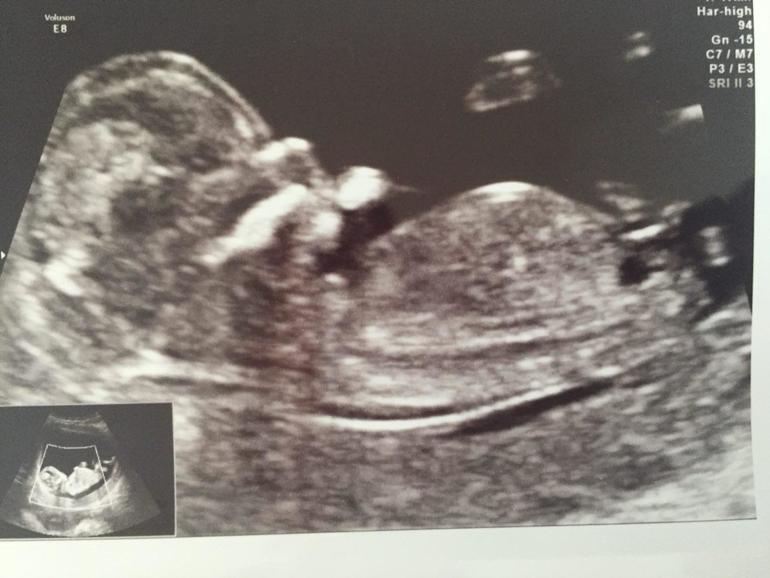

Пол малышаДевочки, кто умеет смотреть половой бугорок, как считаете, кто?

А это малыш внутри, срок 12+3

Врач предположила, но что-то мне совсем не верится. Знаю, что на таком сроке еще не 100%, но та же узист правильно увидела в первый раз, а сейчас не могу ну какак поверить в ее слова. До следующего скрининга изведусь же вся. Ох, ненормальная беременная голова

Кажется, девочка. Они же как-то по углу этого бугорка смотрят. В любом случае, легких родов и здоровья малышу)

Мне на скрининге сказали, что поначалу половой бугорок есть у всех, и у девочек и у мальчиков) а так сделали пока предположение и сказали особо не настраиваться)